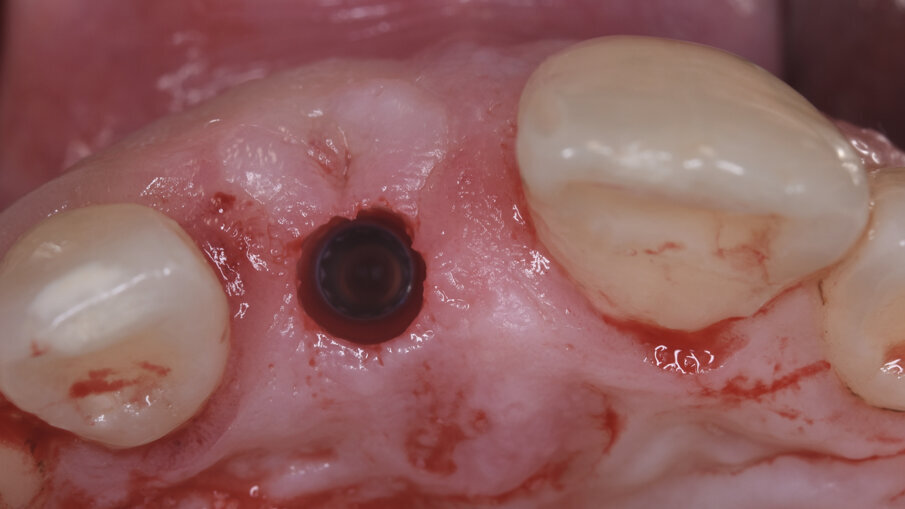

Al momento della chirurgia implantare, con opportuna terapia antibiotica di supporto (2 gr di amoxicillina e acido clavulanico 1 h prima dell’intervento) e dopo anestesia plessica con articaina 1:100.000, si è posizionata la dima chirurgica ed è stato preparato il sito implantare con il kit chirurgico dedicato, con tecnica di sottopreparazione, e posizionato poi l’impianto programmato Imax 3,3x13 (Ires Group Mendrisio [CH]); il torque di inserzione è stato superiore ai 70N/cm e la frequenza di risonanza misurata con Osstel è risultata pari a 75 ISQ, confermando quindi la possibilità di eseguire il carico immediato (Fig. 9).